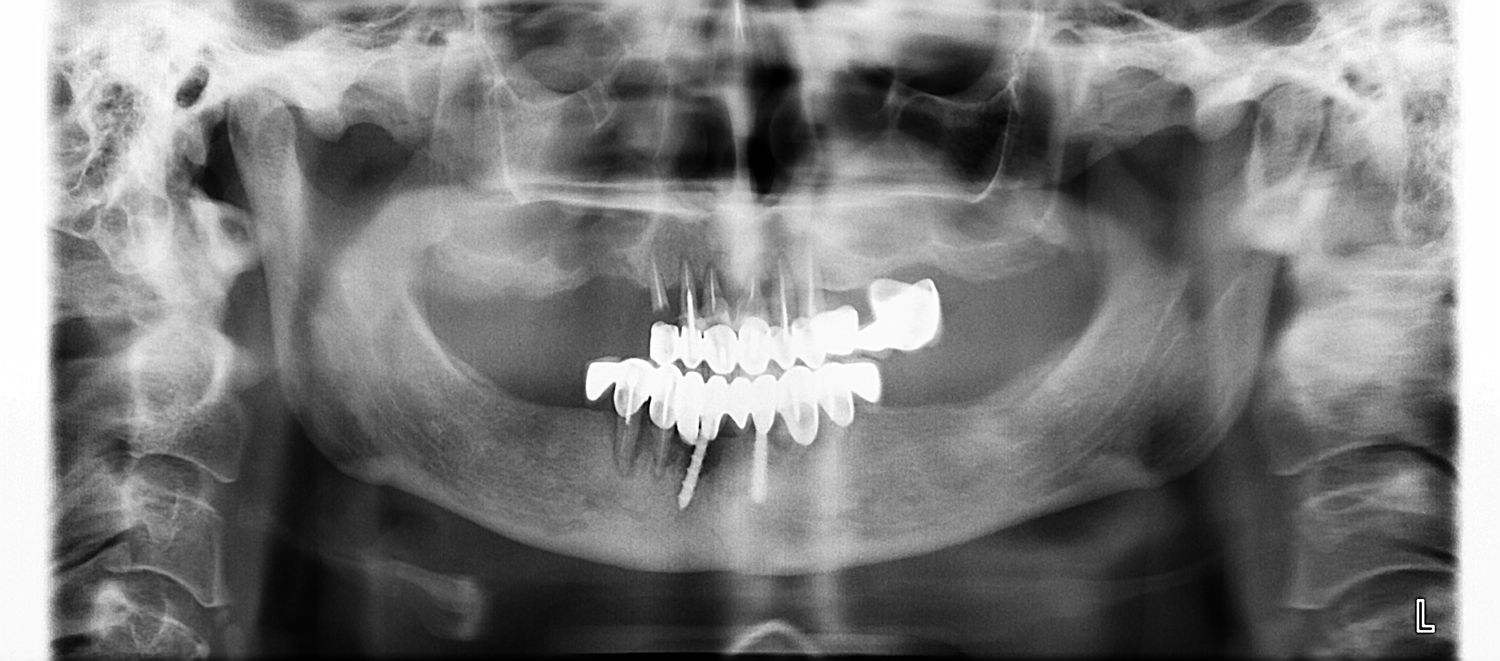

При этих исследованиях мы выяснили, что большинство зубов в полости рта отсутствуют, есть старые коронки, которые расцементировались. Под коронками увидели тёмные пятна – это говорит о том, что зубы под коронками уже практически полностью рассыпались и исчезли. Там же увидели ещё два старых имплантанта, которые реинтегрировались.

На верхней челюсти там же было видно атрофию, отсутствие альвеолярного отростка в области жевательных зубов. Пациентка пришла к нам, потому что не хотела делать операции по наращиванию костной ткани. Также она не хотела делать съемное протезирование. Пациентка захотела сделать быструю реабилитацию с наименьшим количеством оперативных вмешательств и с наименьшими затратами. Мы предложили ей по методике MiMi минимально инвазивной методике имплантации зубов с минимальной инвазивной хирургией с применением лазера удалить зубы и несостоявшиеся импланты. Провести за одно хирургическое вмешательство чистку лунок удалённых зубов лазером. Убрать все инфицированные ткани лазером и убрать воспаления. И сразу установить по 8 односоставных имплантантов на верхней и на нижней челюсти. На верхней челюсти была особенность. Поскольку в области моляров верхней челюсти высота кости была незначительная и была затруднённая установка дентальных имплантантов в этих участках, то были установлены два птеригоидальных имплантанта малоинвазивным способом, а именно в те зоны, верхней челюсти, где кость имеет хорощее питание и атрофия происходит наименьшим способом.

ОПГ до операции